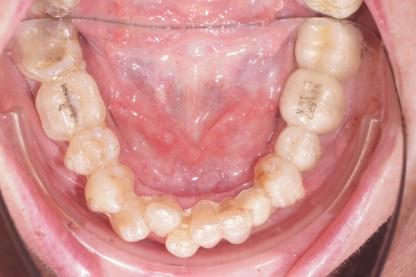

Les aligners

Technique plus récente et très discrète